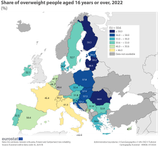

>almost 70 PERCENT of women are OBESE